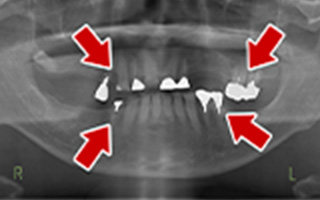

Before

After

| 55歳 男性 | |

|---|---|

| 主訴 | 前歯でしか咬めなく、食事を摂るのに非常に困難で辛い |

| 処置内容 | 上顎6本、下顎3本 |

| 治療費用 | 上顎: 約230万(税込) 下顎: 約120万(税込) |

| 治療期間 | 上顎: 1年(仮歯まで8ヶ月) 下顎: 8ヶ月(仮歯まで5ヶ月) |

| リスク | 上部構造物、仮歯の破折、術後の腫れ(3日)、人工歯根脱落リスクがあります |